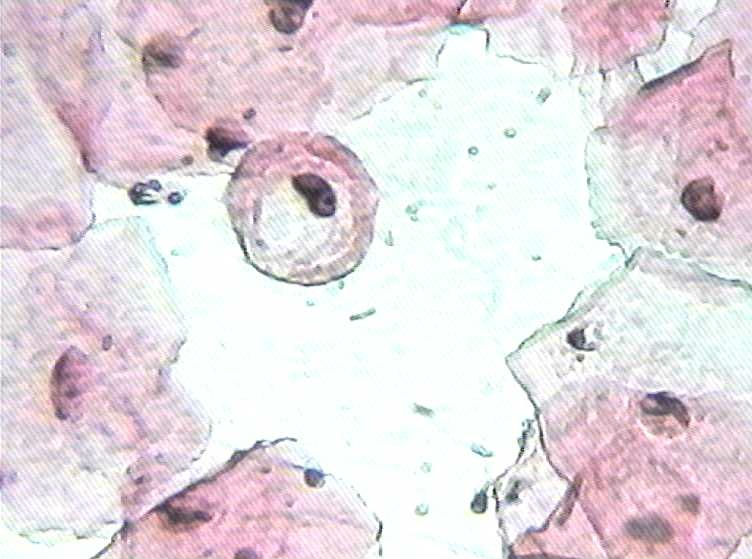

大家看看这是不是挖空细胞

大家看看这是不是挖空细胞图1

描述:挖空1

是不是挖空细胞?一张片子里太多这样的细胞了

不太清楚,可能是吧

这一张片子里太多这样的细胞了,但临床上又没发现有这种症状

可以结合HPV基因分型确定。

会不会有一些其它的因素造成整张片这么多的挖空细胞?

从我觉得不像,核周空晕不够透亮,另外,感觉这个片子怪怪 ,像没有封片的样子。

真是高手,是没有封片,

老年人的细胞经常有类似挖空的细胞,感觉挖空的面积太大,而且细胞核也没多大异性表现。

个人观点:不是挖空细胞。没有见到异型细胞核。

图3和图5可能是控空细胞,其余细胞核小了点,边缘胞浆深染处可能是卷折造成的。

不是挖空细胞。典型的挖空细胞透亮如背景色,空得不规则,核有异型。